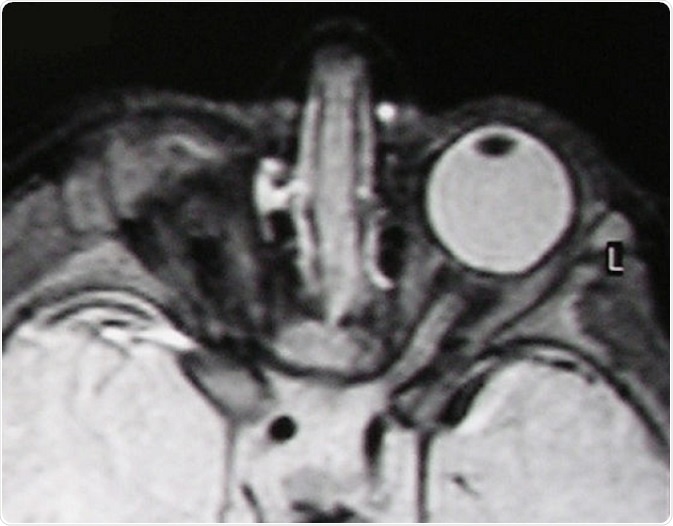

For example, some genetic mutations lead to anophthalmia (one or no eyes present) or microphthalmia (abnormally small eyes) whereas others lead to cell-specific defects like the absence of rods or cones at the back of the eye, the cells (photoreceptors) that are responsible for detecting light.

T2-weighted MR scan of a patient with unilateral anophthalmia. Note the presence of amorphous tissue and structures resembling extraocular muscles within the anophthalmic right orbit. The right optic nerve/chiasm junction appears attenuated rather than absent suggesting possible residual optic nerve neural tissue. © Verma AS / Wikimedia Commons.